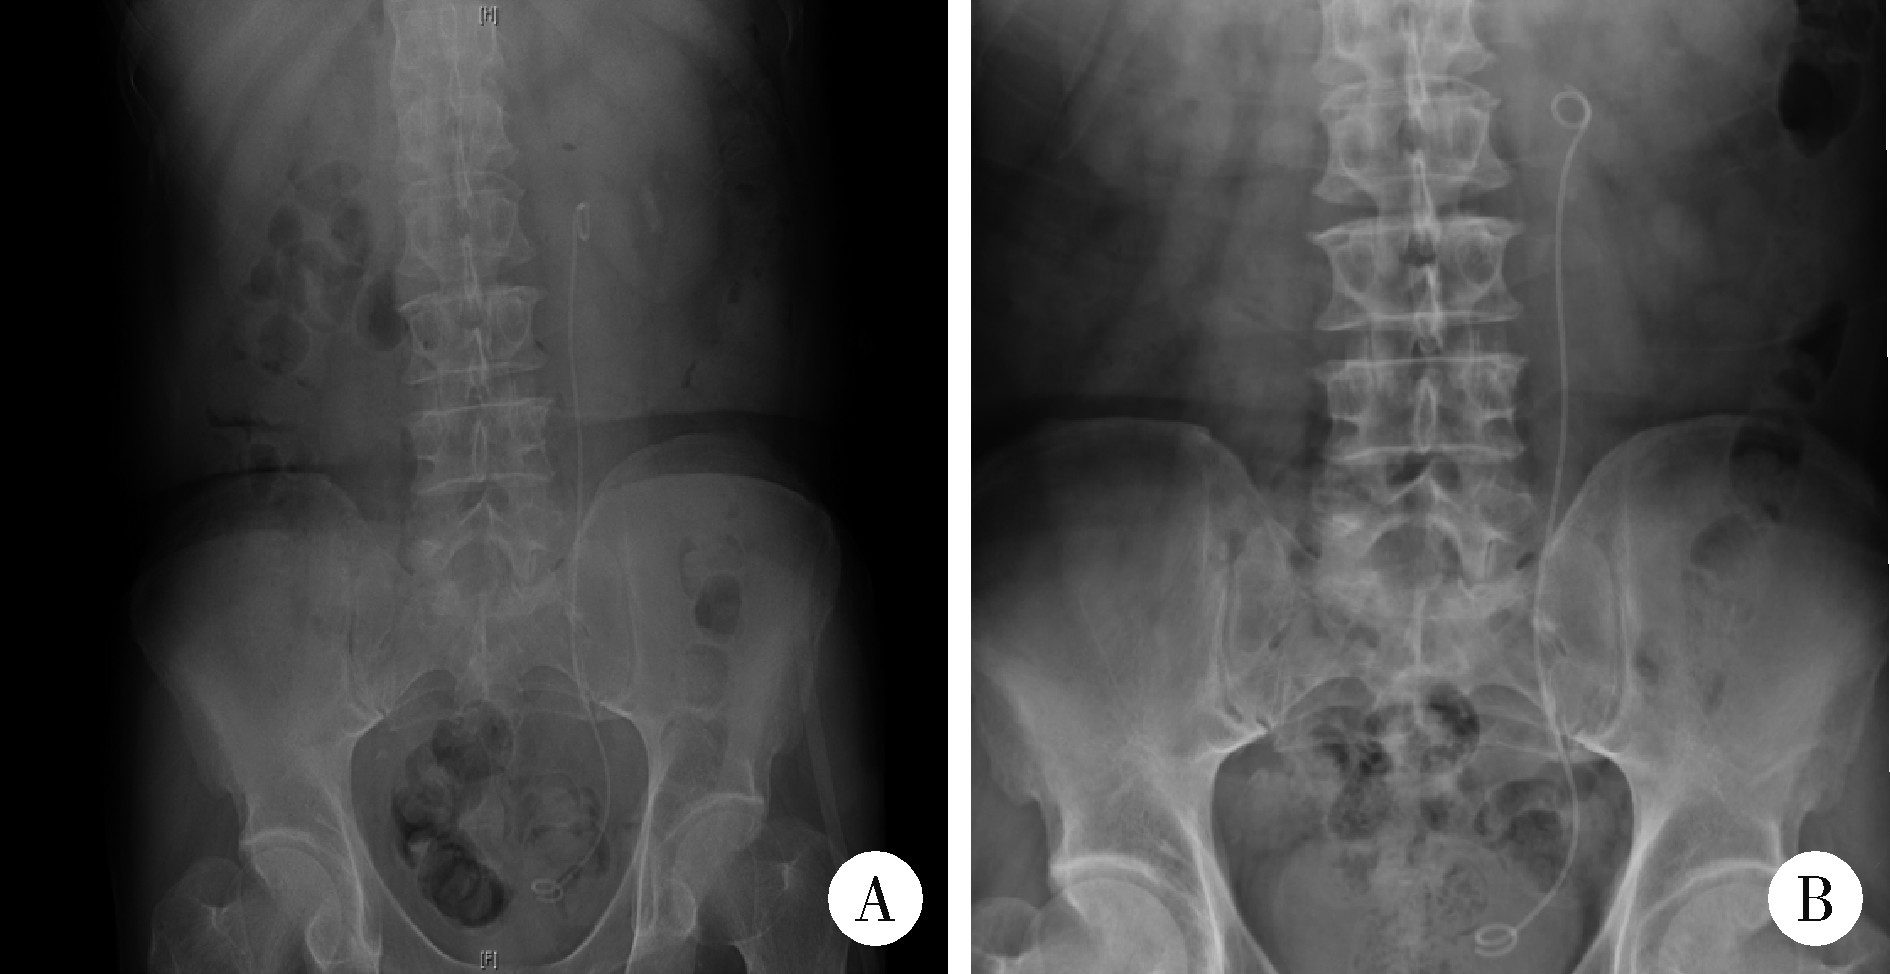

Figure 3

KUB after RULL + N-trap A, KUB finished on 1 d after RULL + N-trap; B, KUB finished in 1 month after RULL + N-trap. KUB, kidneys, ureters and bladders; RULL + N-trap, rigid ureteroscopic laser lithotripsy combined with N-trap."